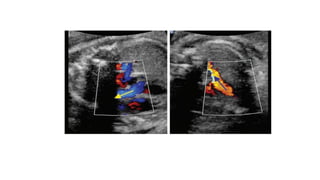

• #22 The three-vessel view. In this view, one can identify the three vessels from left to right (A) or anterior to posterior (B) as pulmonary artery (PA), aorta (A) and superior vena cava (V). The sizes of the pulmonary artery and aorta can be compared with the PA slightly larger than the aorta